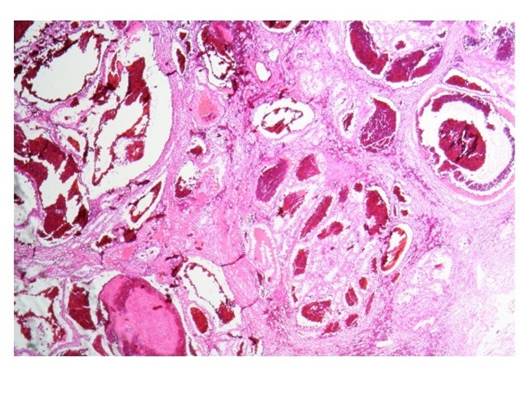

El rodete vesical sin displasia o lesión (borde quirúrgico libre). La pieza de patología del lado izquierdo confirma un carcinoma de células renales claras G1 confinada al parénquima renal sin identificar invasión linfovascular o a la cápsula de Gerota (Imagen 7 y 8), no se identifican características rabdoides o sarcomatoides y está localizado a 0.6 cm del borde quirúrgico (borde quirúrgico libre).